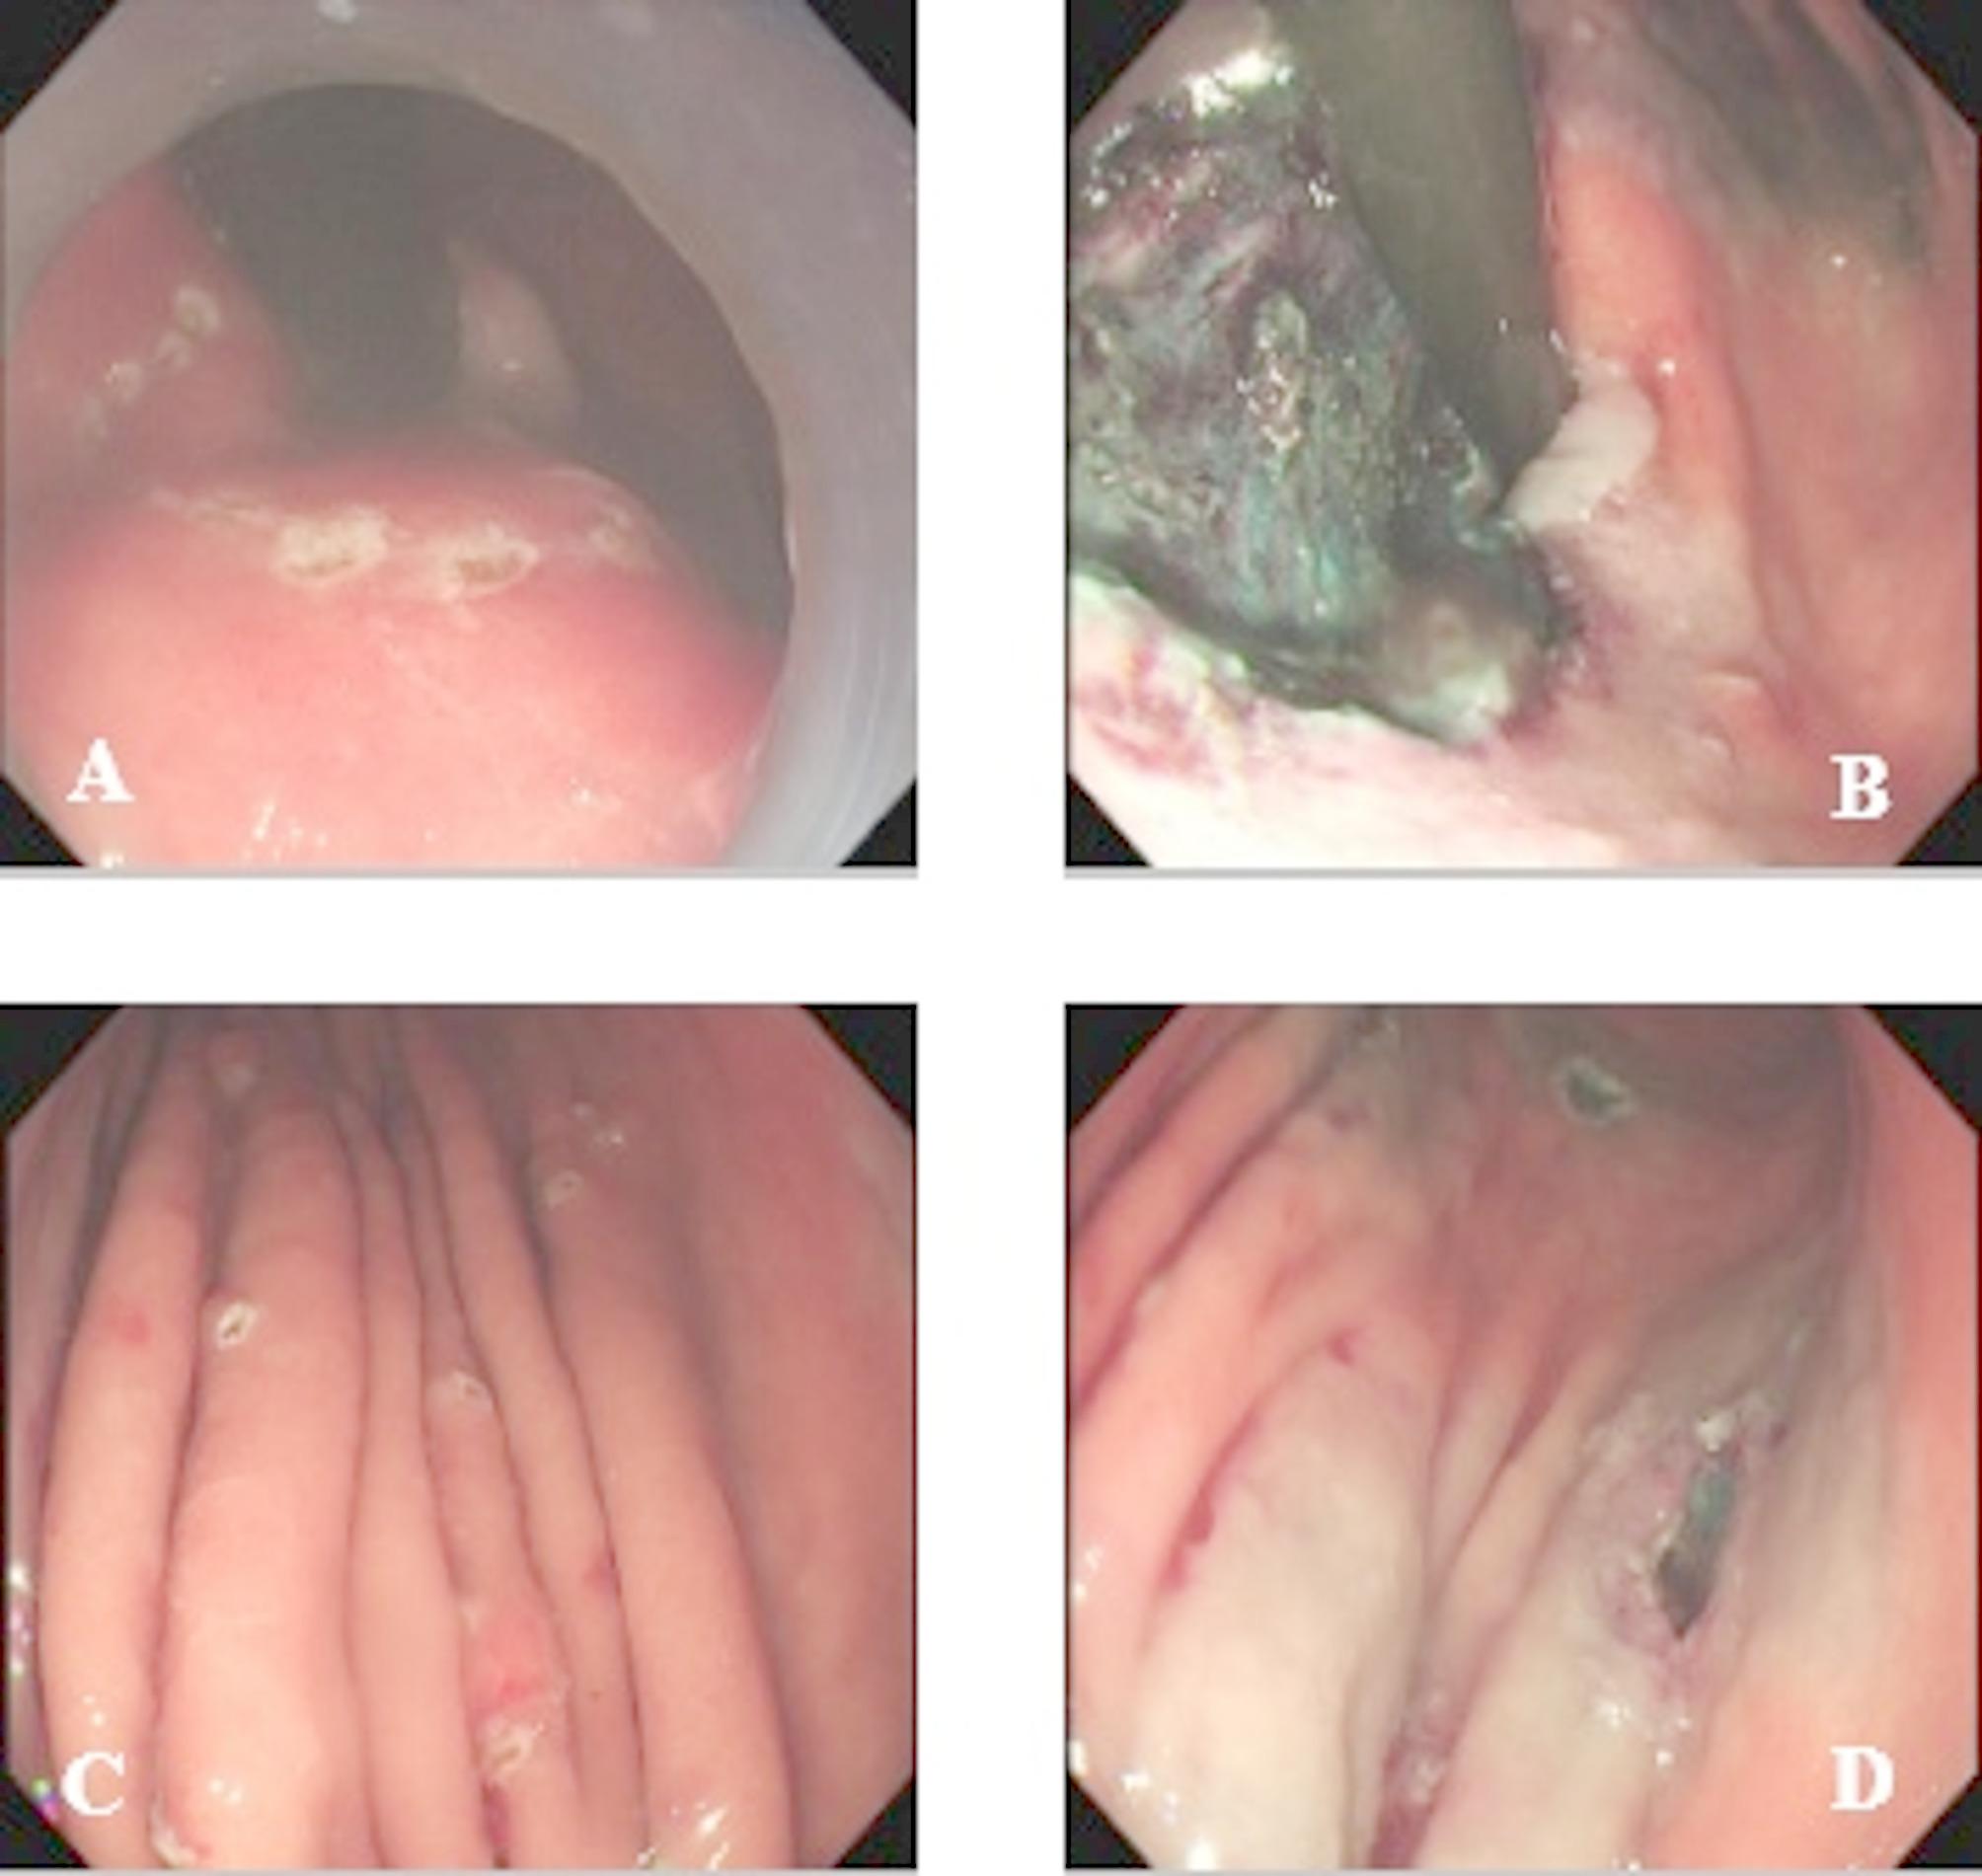

Concomitant gastric cancer and neuroendocrine tumours in the stomach: a rare case series of 3 patients and a literature review.

{"title":"Concomitant gastric cancer and neuroendocrine tumours in the stomach: a rare case series of 3 patients and a literature review.","authors":"Luyu Liu, Weilu Ding, Zhenzhen Wang, Gongning Wang, Limian Er","doi":"10.1186/s13000-025-01704-4","DOIUrl":null,"url":null,"abstract":"","PeriodicalId":11237,"journal":{"name":"Diagnostic Pathology","volume":"20 1","pages":"100"},"PeriodicalIF":2.3000,"publicationDate":"2025-08-29","publicationTypes":"Journal Article","fieldsOfStudy":null,"isOpenAccess":false,"openAccessPdf":"https://www.ncbi.nlm.nih.gov/pmc/articles/PMC12395632/pdf/","citationCount":"0","resultStr":null,"platform":"Semanticscholar","paperid":null,"PeriodicalName":"Diagnostic Pathology","FirstCategoryId":"3","ListUrlMain":"https://doi.org/10.1186/s13000-025-01704-4","RegionNum":3,"RegionCategory":"医学","ArticlePicture":[],"TitleCN":null,"AbstractTextCN":null,"PMCID":null,"EPubDate":"","PubModel":"","JCR":"Q2","JCRName":"PATHOLOGY","Score":null,"Total":0}